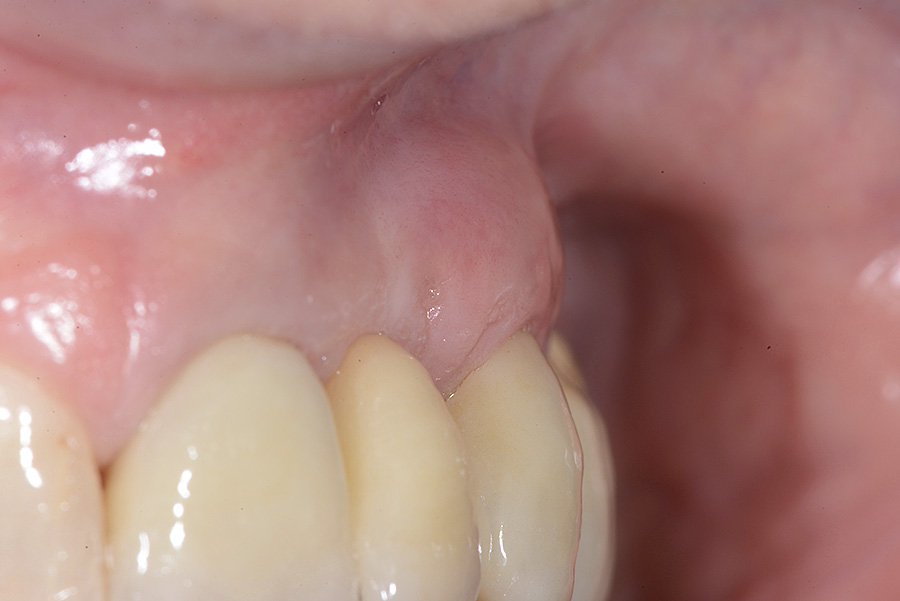

PREMESSA: in seguito all’estrazione dell’incisivo laterale superiore di destra, resasi necessaria per cause batteriche, si decide di affrontare il caso con il posizionamento di un impianto in sostituzione dell’elemento mancante dopo guarigione del sito infetto. Con tecniche rigenerative sia dei tessuti ossei mancanti a causa dell’infezione pregressa, sia dei tessuti gengivali che appaiono inizialmente troppo spostati in alto, si ripristina una corretta morfologia delle parabole (contorni) gengivali e delle papille interdentali (triangoli di gengiva tra due denti vicini).

Vengono utilizzati 2 tipi di provvisori: il primo, cementato ai denti vicini, viene utilizzato dal momento dell’estrazione del dente fino ad impianto osteointegrato (circa 6 mesi); il secondo, avvitato direttamente all’impianto, ha una funzione di prova estetica ma soprattutto di guida per la maturazione dei tessuti gengivali peri-implantari portandoli verso la maturazione completa prima di posizionare la corona finale in disilicato di litio.